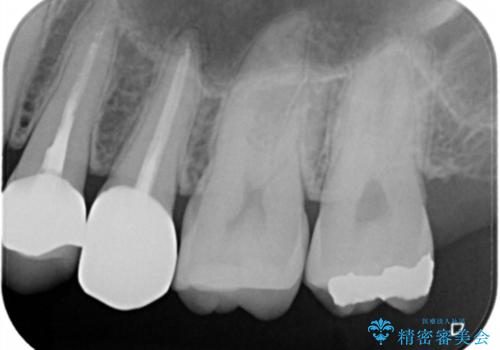

う蝕除去中に露髄 フルジルコニアクラウン

う蝕除去中に露髄したため精密根管治療へと切り替え、仮歯をはさんでセラミッククラウンを装着し終了としました。

*根管治療は保険を希望されました。